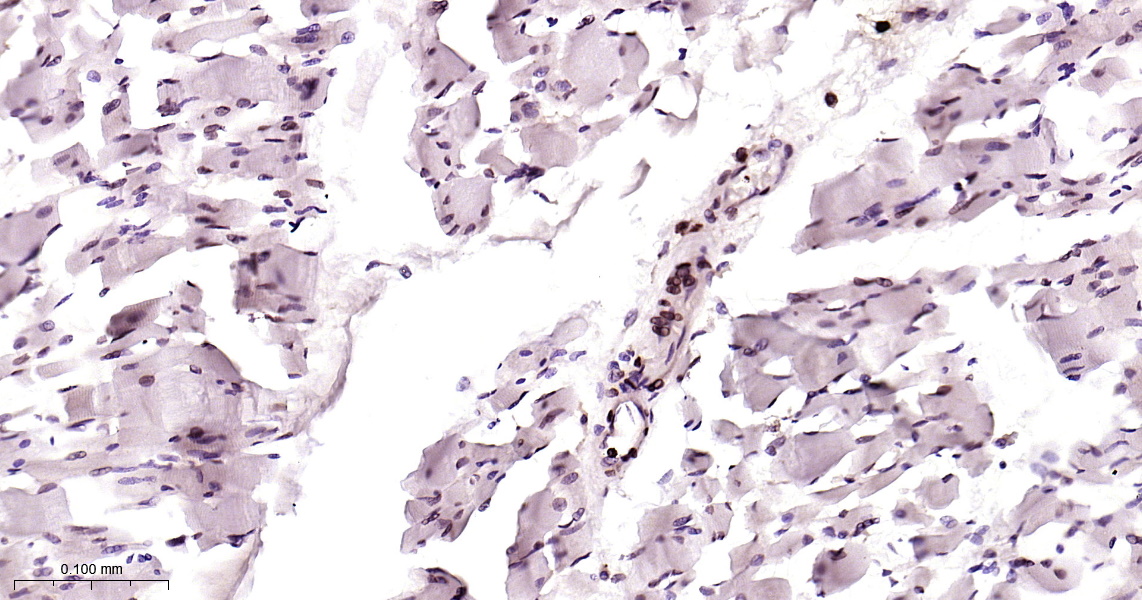

Emerin Recombinant Antibody

• IHC-P

IHC-P IHC-P1:100-500